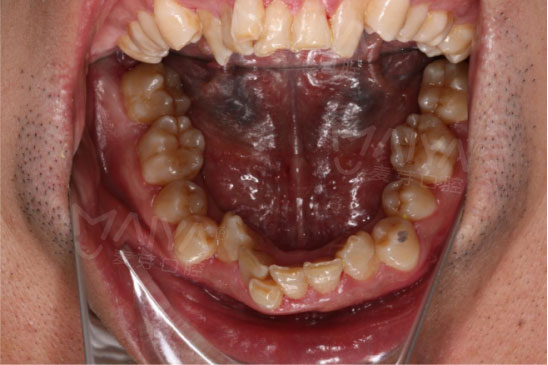

我的牙齿到底可怕到什么程度?前方高能预警———不要被吓到哦

男人不需要注重仪表?

身为公司管理层,平时待人接物不仅仅代表自己,还代表着公司形象,一口鲨鱼牙怎能为麦芽代言?而且注重仪表的我,怎能允许自己在洽谈时露出钢牙套?于是我决定立即在麦芽开始隐形矫牙之旅。